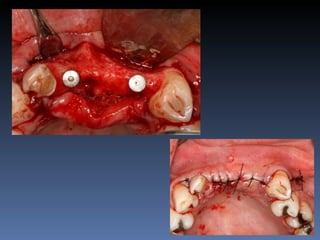

BOX 3

Vanda Alves da Silva

Idade – 51 anos

Sexo – Feminino

Raça – Caucasiana

ASA – II

Data- 26-04-2012

Diagnóstico: Desdentada parcial

Bimaxilar, periodontite 3.1

com mobilidade grau 3.

Plano de tratamento: Exodontia 3.1 , seguida de

instalação de implante com função imediata e

reabilitação provisória fixa.

Isolamento da área cirúrgica com luva estéril.